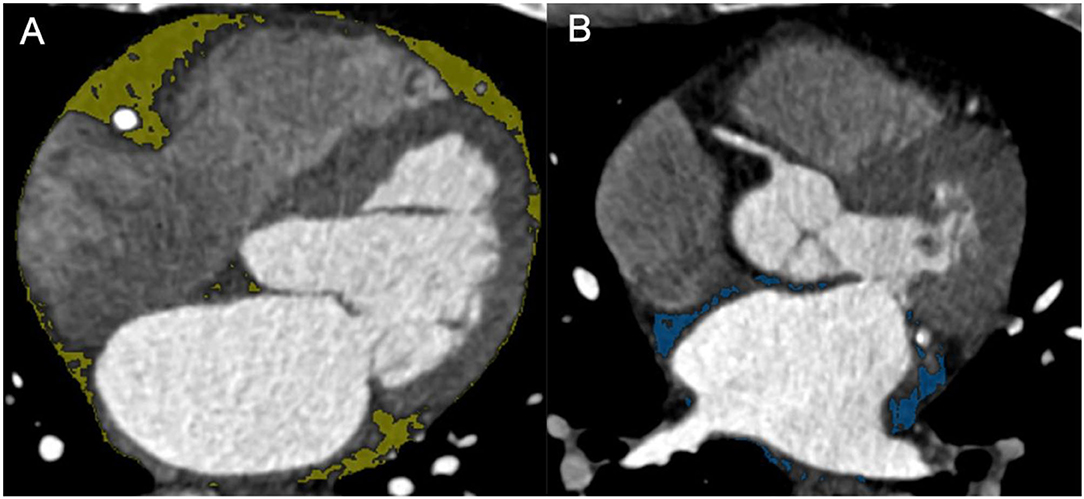

The EAT and LA-EAT were measured using the commercial post-processing workstation (SyngoVia, VB20, Siemens Healthineers, Forchheim, Germany). We adopted software (Cardiac risk analysis, SyngoVia, Research Frontier, Siemens Healthineers) to segment EAT automatically, and checked by two radiologists, who were blinded to the patients' clinical history. To delineate LA-EAT, we loaded the EAT mask into the Radiomics software (SyngoVia, Research Frontier, Siemens Healthineers) (24). Initially, the LA-EAT mask was manually tracked on the axial image, the upper boundary is the pulmonary artery, the lower boundary is the coronary sinus, and manually trimmed using EAT as a reference. Then, LA-EAT was automatically identified using the threshold of −200 to −50 HU. Meanwhile, the EAT and LA-EAT volumes in cubic centimeters were measured (Figure 3).

Figure 3. (A) EAT. (B) LA-EAT. EAT, epicardial adipose tissue; LA-EAT, epicardial adipose tissue surrounding the left atrium.